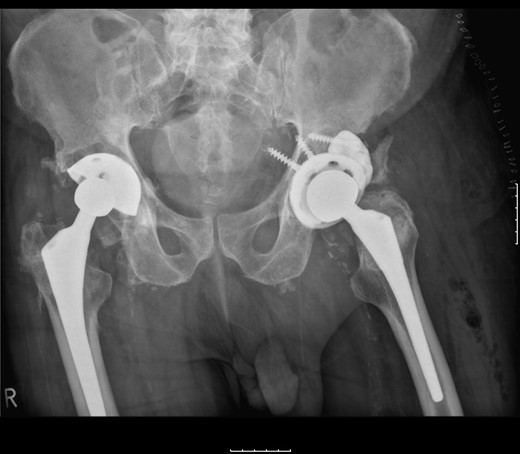

The femoral stem was kept firm in its proper position. Structural porous titanium acetabular augment (Regenerex™), reinforced with a cancellous allogeneic bone graft, was used to reconstruct the superior acetabular wall. The cup was completely revised using a Biomet® Regenerex Ringloc® multihole 56-mm acetabular cup and a Hi-wall Ringloc-x PE 54-mm liner. The previous 32-mm femoral head was replaced with a Bioball® 36-mm metal head and a Bioball® adapter standard (0 mm) Taper 11/13 (4° 3°), correcting the offset and achieving stability (Fig. 4).

A post-revision radiograph demonstrating a structural graft using the acetabular augment (Regenerex™) and revised cup in situ.